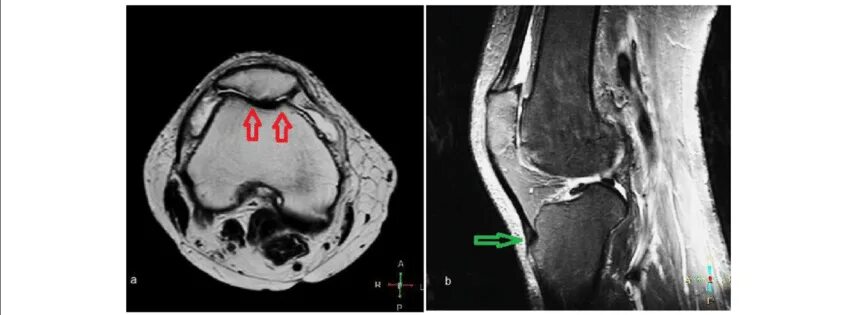

Повреждение хряща по outerbridge